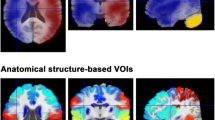

Inadequate blood supply relative to metabolic demand, a haemodynamic condition termed as misery perfusion, often occurs in conjunction with acute ischaemic stroke. Misery perfusion results in adaptive changes in cerebral physiology including increased cerebral blood volume (CBV) and oxygen extraction ratio (OER) to secure substrate supply for the brain. It has been suggested that the presence of misery perfusion may be an indication of reversible ischaemia, thus detection of this condition may have clinical impact in acute stroke imaging. The ability of single spin echo T2 to detect misery perfusion in the rat brain at 1.5 T owing to its sensitivity to blood oxygenation level dependent (BOLD) contrast was studied both theoretically and experimentally. Based on the known physiology of misery perfusion, tissue morphometry and blood relaxation data, T2 behaviour in misery perfusion was simulated. The interpretation of these computations was experimentally assessed by quantifying T2 in a rat model for cerebral misery perfusion. CBF was quantified with the H2 clearance method. A drop of CBF from 58 ± 8 to 17 ± 3 ml/100 g min in the parieto-frontal cortex caused shortening of T2. from 66.9 ± 0.4 to 64.6 ± 0.5 ms. Under these conditions, no change in diffusion MRI was detected. In contrast, the cortex with CBF of 42 ± 7 ml/100 g min showed no change in T2. Computer simulations accurately predicted these T2, responses. The present study shows that the acute drop of CBF by 70% causes a negative BOLD that is readily detectable by T2 MRI at 1.5 T. Thus BOLD may serve as an index of misery perfusion thus revealing viable tissue with increased OER.